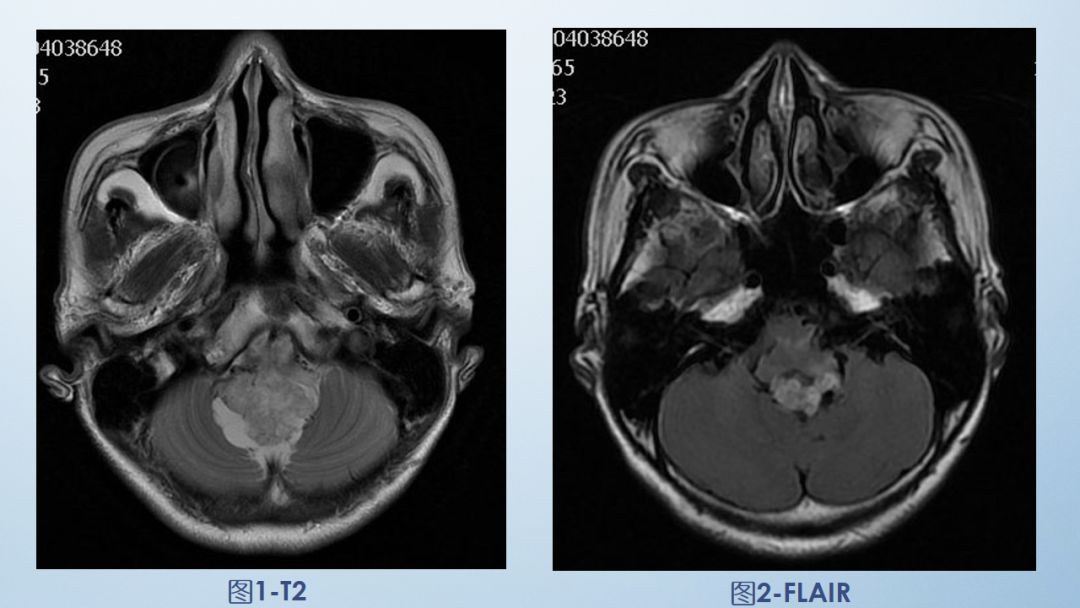

图9为所示病例同层面轴位正常T2WI图片,双侧小脑半球对称(白色箭头)、桥脑(黄色箭头)、小脑中脚(蓝色箭头)、第四脑室(棕色箭头)。后颅窝主要由枕骨和颞骨岩部后面共同组成,其内主要包含小脑半球、脑干、前庭神经等。

双侧小脑半球对称存在,与桥脑通过三对小脑脚相连(本图可见小脑中脚),前庭神经通过内听道走行,桥脑前侧为桥前池及双侧桥小脑角池,桥脑后侧、双侧小脑中脚、双侧小脑半球、小脑蚓部共同围绕第四脑室。